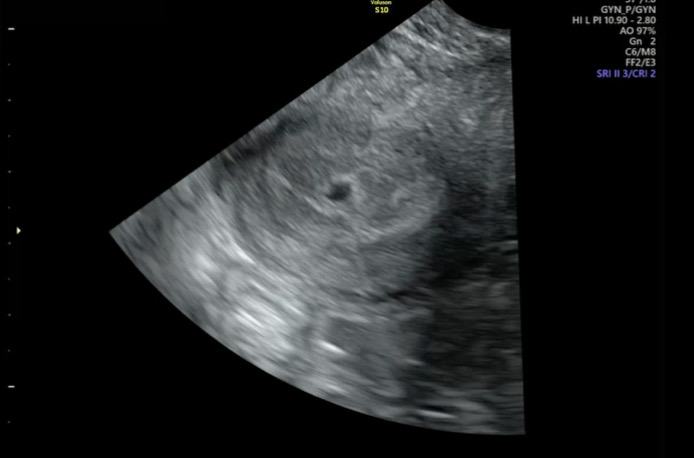

5주 4일차입니다 !! 지난 주말에 아기집 확인했고 아직까지는 입덧이나 통증이 심하지는 않은데 가끔가다 생리통처럼 배가 살살아프고 허리가 조금 아프네요 ㅠㅠ 내일 친구들이랑 강릉여행 약속이 잡혀있는데 제가 사는 곳이 지방이라 시외버스타고 편도 5시간 입니다. 친구들은 잘챙겨주겠다고 그래도 무리하지 않으면 괜찮지 않냐고 하면서 꼭 놀러오라고 하던데.. 오늘은 샤워할때도 점점 숨이차고 움직이는게 예전처럼 편하지 않았어서 왠지 내일 놀러가서 친구들에게 민폐만 끼치는건 아닌지, 아니면 아기에게 무리가 되는 건 아닌지 고민이 이만저만이 아니네요 ㅠㅠ 어떻게 하면 좋을까요 ㅠㅠㅠ…